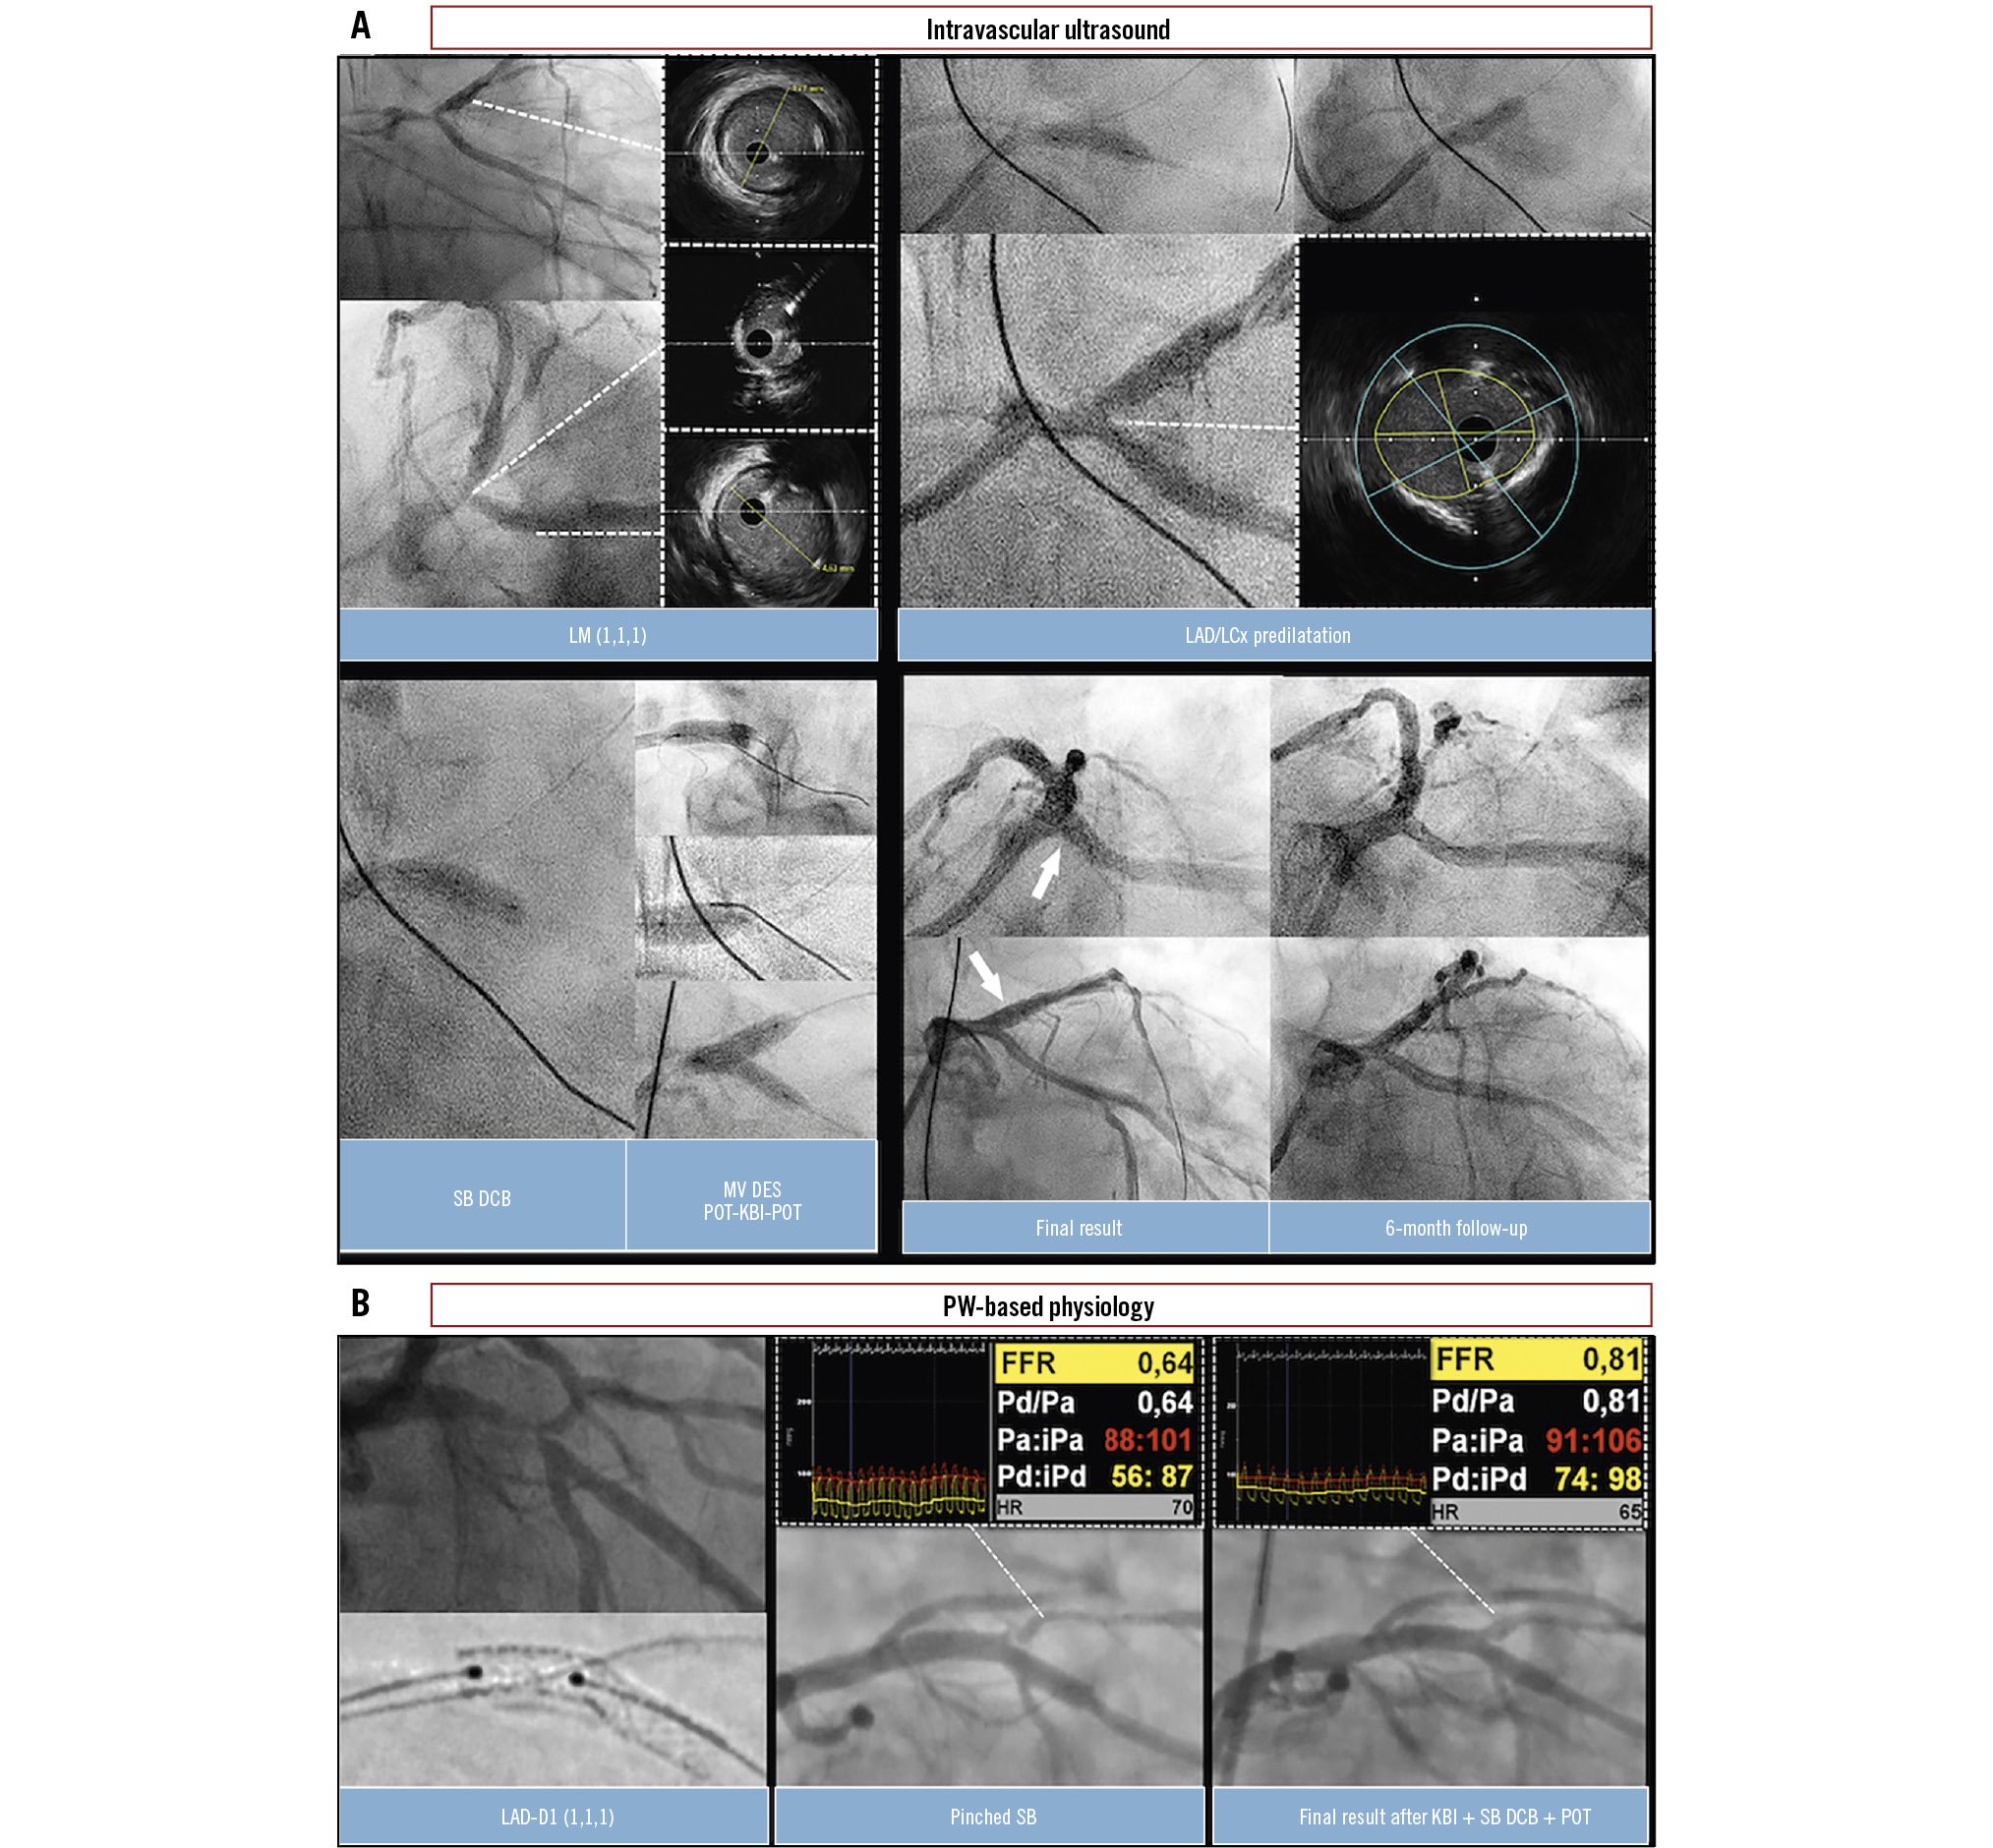

The blended/hybrid approach to CBLs inherently integrates the use of DCBs in the provisional DES implantation philosophy, allowing for a reduction in the overall stent burden and providing angiographic and clinical advantages compared to POBA alone. SB treatment with a DCB can be delivered either before or after DES implantation across the SB. In the former case, a DCB is first applied to the side branch, followed by DES implantation in the main vessel, after which the mandatory proximal optimisation technique (POT) is performed (Figure 3, Figure 4A). In case of a suboptimal SB result, the procedure may be continued either with kissing balloon inflation (KBI) and re-POT or POT-side-POT inflations. Theoretically, these further inflations might interact with the antiproliferative drug that has already been delivered to the SB. In the latter case, DCB treatment is performed as a final step following DES implantation across the SB, POT, SB rewiring and dilatation, DCB application to the SB, followed by optional KBI and mandatory final re-POT (Figure 4B, Figure 5). It has been postulated that such an approach might be associated with suboptimal drug delivery, as the interaction with the DCB and stent struts might lead to drug loss and hamper proper drug delivery to the SB. Furthermore, the deliverability of cutting or scoring balloons, which is inherently limited because of their device profile and mechanical characteristics, is further compromised in the setting of a jailed SB, potentially affecting adequate lesion preparation. It should be noted that the timing and sequence for DCB use in bifurcation PCI remain topics of ongoing debate, as robust evidence to guide these decisions is currently limited. Current recommendations are largely based on expert opinion and clinical experience, emphasising the need for further large prospective randomised studies to establish more definitive guidance.

Figure 4. Coronary physiology and intravascular imaging guidance for a DCB/DES blended approach. A) A case of LM CBL (Medina 1,1,1). IVUS initially revealed a significant stenosis at the ostium of the LCx. Lesion preparation was performed using a 4.0 mm cutting balloon to predilatate the LAD, LCx, and LM. Following predilatation, the IVUS result in the LCx was deemed satisfactory, with restored flow and less than 30% recoil. However, IVUS assessment indicated unacceptable recoil in the LM segment. A 4.0×15 mm paclitaxel-coated DCB was first applied to the LCx for 30 seconds. Subsequently, a provisional DES implantation (5.0×16 mm) was performed from the LM ostium into the LAD. POT was then performed using a 5.5×6 mm NC balloon, followed by KBI (4.0 mm in the LAD, 3.5 mm in the LCx) and final POT. The final angiographic and IVUS results were satisfactory, showing minimal lumen areas of 14 mm² in the LAD, 7.7 mm² in the LCx, and 19.5 mm² in the LM. Three-month follow-up angiography confirmed a durable and favourable result of this blended approach. B) A case of LAD-D1 CBL (Medina 1,1,1). Following lesion preparation of the MV with NC balloons, a DES (3.5×22 mm) was implanted across the D1 using a provisional approach. POT was then performed with a 4.0×8 mm NC balloon. Subsequent angiography revealed a pinched SB with ischaemic FFR values (FFR 0.64) in the D1. After rewiring the SB, KBI was performed using 3.0 mm and 2.5 mm NC balloons, followed by inflation of a paclitaxel-coated DCB (2.5×20 mm) in the SB and the mandatory final re-POT. This strategy resulted in a favourable angiographic outcome and marked functional improvement, with FFR increasing to 0.81. CBL: coronary bifurcation lesion; D1: first diagonal branch; DCB: drug-coated balloon; DES: drug-eluting stent; FFR: fractional flow reserve; IVUS: intravascular ultrasound; KBI: kissing balloon inflation; LAD: left anterior descending artery; LCx: left circumflex artery; LM: left main; MV: main vessel; NC: non-compliant balloon; POT: proximal optimisation technique; PW: pressure wire; SB: side branch